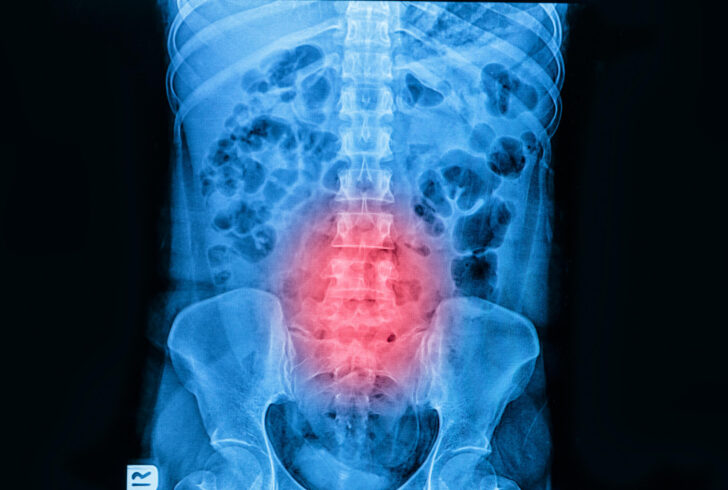

X線・MRIで確認できること

圧迫骨折の診断では、X線検査やMRI検査が用いられます。X線検査では椎体の変形の有無を確認できますが、骨折直後では変化が分かりにくい場合もあります。

一方MRI検査では、圧迫骨折により骨の内側に生じた炎症や出血の状態を捉えることができ、今起きている新しい骨折かどうかを判断するのに役立ちます。MRIは圧迫骨折後の治療方針を決定するうえで重要な情報となり、保存療法を続けるか、骨セメント療法を検討するかの判断材料になります。